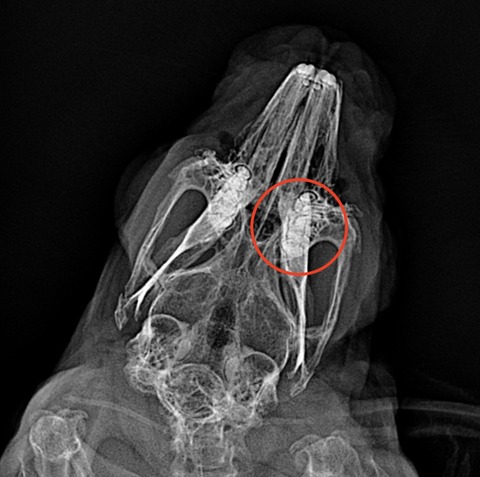

では歯並びが歪んでるとはどういうことかを、レントゲン画像でご紹介します

⇩これが不揃いの子だと

歯根が揃ってないのがわかるかと思います、こういう歯根の子では現状問題なくても膿瘍の発生が警戒されます

健康診断時には歯のレントゲンを撮ってもらっても良いのかもしれませんね

横向けにウサギを寝かせて上からX線を照射し撮影しているので、左右の歯が重なってしまい完璧な評価ができる訳ではないですが、参考にはなります

(理想的にはCTで全ての歯根をチェックするのが望ましい)

歯根の炎症が慢性化すると、歯も変性して濃い白で写ってくるようになります